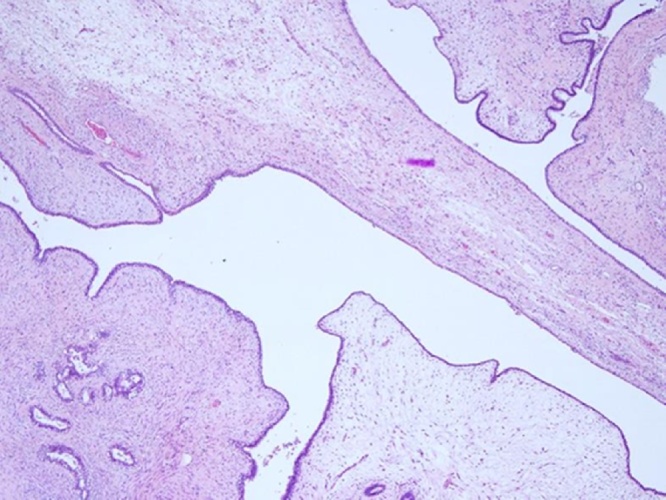

She underwent a core biopsy of the left breast mass and left axilla lymph node. The left breast mass biopsy showed a cellular fibro epithelial lesion with mild increase in stromal cellularity. No stromal atypia or mitoses were seen (Fig. 3). The left axilla lymph node returned as sinus histiocytosis, no malignancy was seen. She was referred to an ENT surgeon and a fine needle aspiration of the parotid lump returned as malignant cells.

Fig. 3.

Core biopsy of left breast mass show a cellular fibroepithelial lesion. The intervening stroma is mildly cellular. H & E 40X.

The final histology returned as completely excised benign phyllodes. All 7 sampled axillary lymph nodes were negative for malignancy. The mastectomy specimen (Fig. 4) was largely replaced by a pinkish lobulated and fleshy mass with foci of cystic change. It measured 187 mm (ML) × 190 mm (SI) × 80 mm (AP). The features were of a cellular fibroepithelial lesion with predominantly a well circumscribed margin which only focally exhibited a pushing edge (Fig. 5). The lesion comprised breast ducts separated by a mildly cellular stroma which exhibited a phyllodial architecture with slit like compressed ducts imparting a leaf like architecture (Fig. 6). There was no stromal atypia or increased mitoses or stromal overgrowth thus it was consistent with findings of a benign phyllodes tumour.

Fig. 6.

Leaf like (phyllodial architecture) of the lesion; H & E 40x.

The term “phyllodes” means leaf like and refers to the papillary projections that are seen on microscopic examination [6]. The diagnosis of phyllodes has been well established in the recommendations of WHO [7]. It is diagnosed when the fibroepithelial architecture shows an exaggerated intracanalicular pattern with leaf like fronds protruding into cystically dilated spaces accompanied by hypercellularity. A benign phyllodes tumour is characterized by mildly increased stromal cellularity and irregular borders. In contrast, a fibroadenoma whilst may have increased stromal cellularity usually has a circumscribed margin but this cannot be assessed on the biopsy. Therefore it may be difficult to distinguish a fibroadenoma and phyllodes tumour on biopsy. Furthermore, the distinction of benign and borderline phyllodes using the criteria of increased stromal cellularity, stromal atypia and mitoses can be very subjective and hence the accurate diagnosis is usually made only on the excision specimen. A malignant phyllodes tumour is distinguished from a benign/borderline phyllodes tumour by the presence of marked stromal cellularity, cellular atypia, permeative margins and mitotic activity of at least 10/10 HPF. However, because there is no objective criterion to distinguish stromal hypercellularity and atypia, the pre-operative diagnosis of phyllodes tumour may not always be possible, as seen in our patient case.